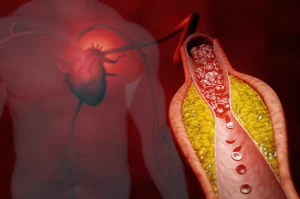

Doenças arteriais

Acompanhar a saúde das suas artérias é fundamental, especialmente se você já passou dos 50 anos ou tem histórico de problemas circulatórios.